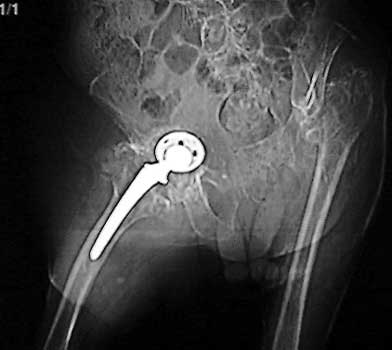

INFECTION—Markedly widened interfaces about acetabular and femoral components